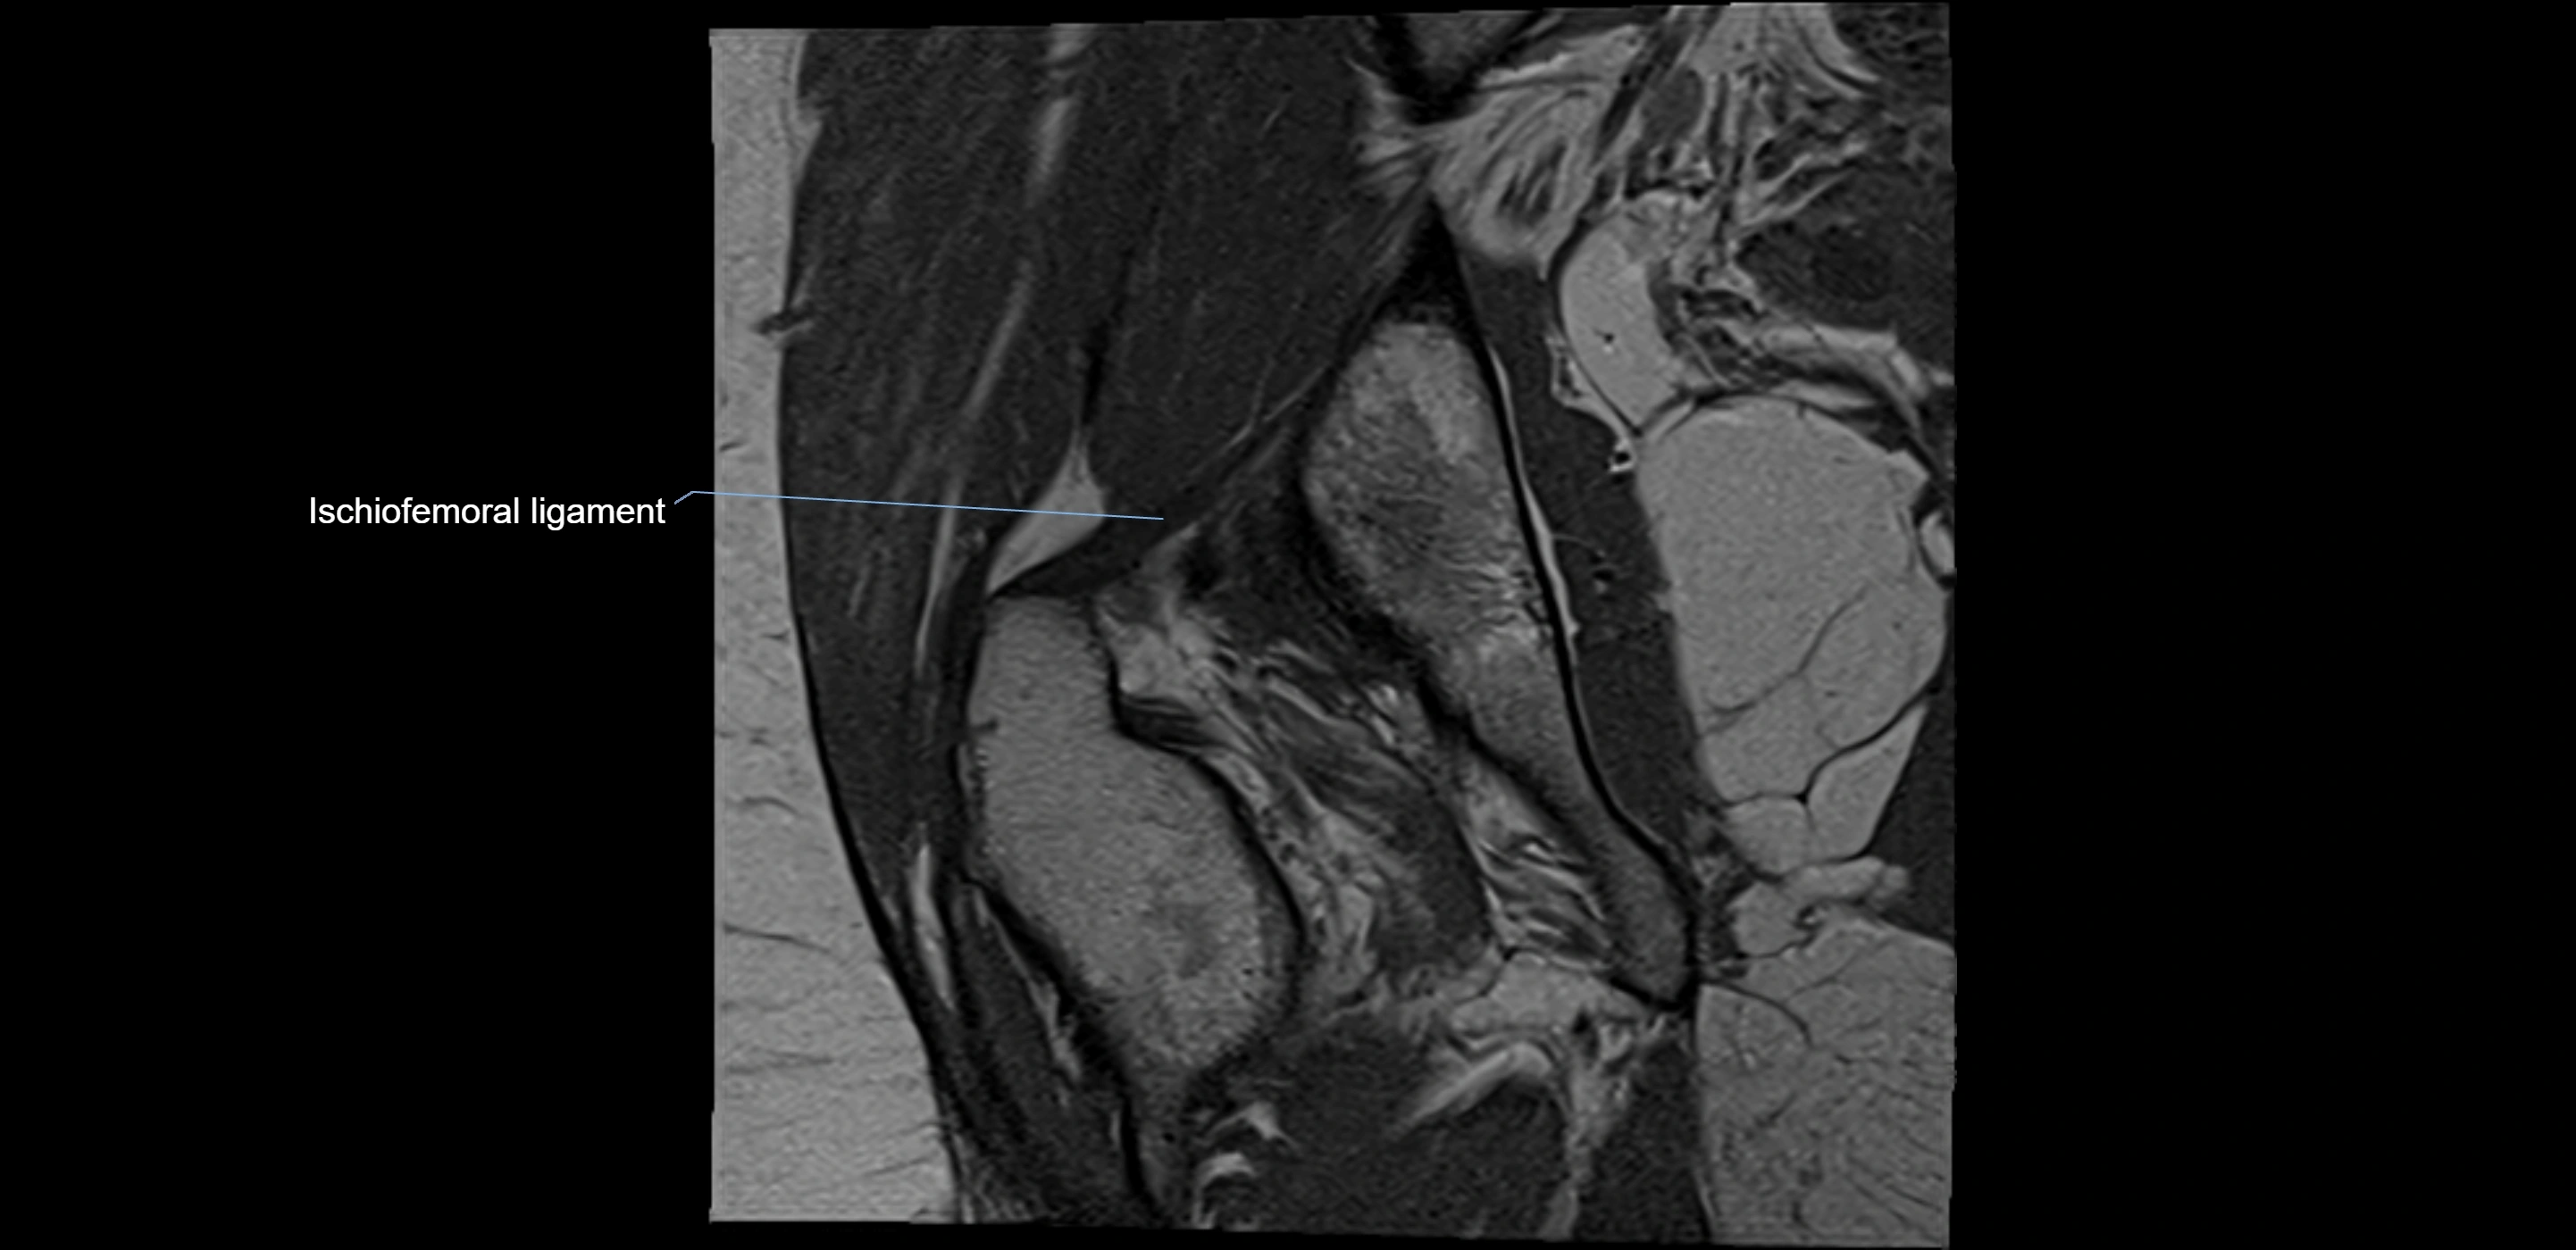

MRI Appearance

T1-weighted images:

• Labrum: low signal intensity (dark)

• Surrounded by intermediate signal joint fluid (bright on arthrogram)

• Tears: linear or focal areas of intermediate-to-high signal interrupting labral continuity

T2-weighted images:

• Joint fluid: bright, making labral tears visible as fluid extending into or around labrum

MRI image

image